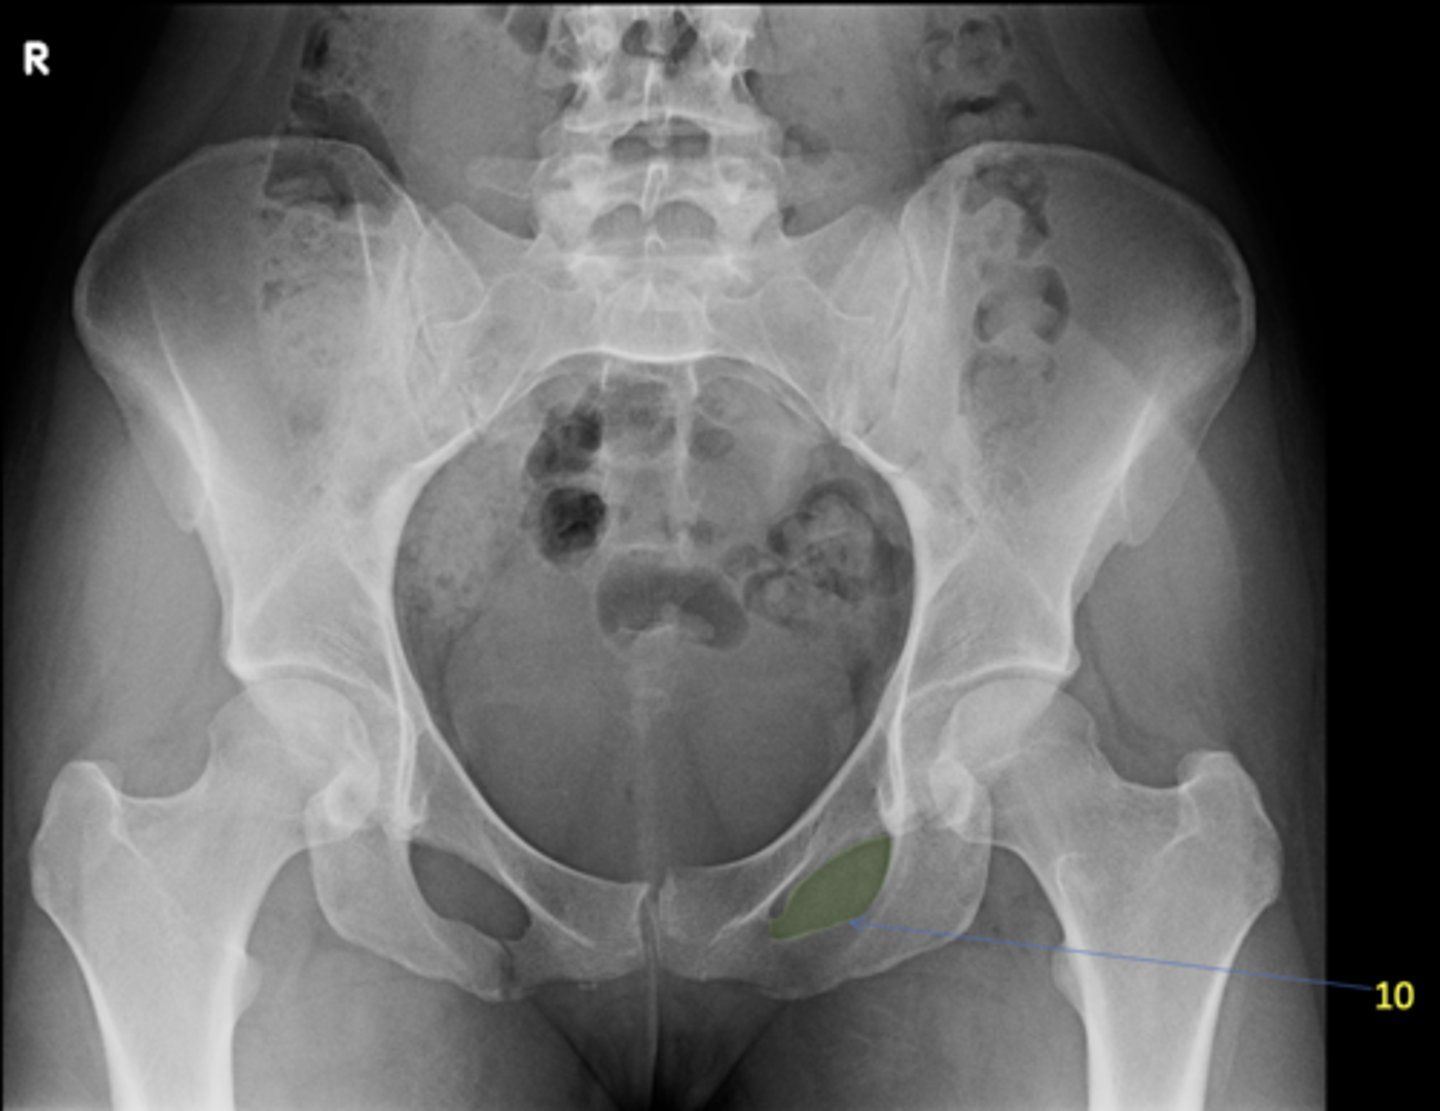

1

AP pelvis

View?

10

Left obturator foramen

ID 10

<p>ID 10</p>